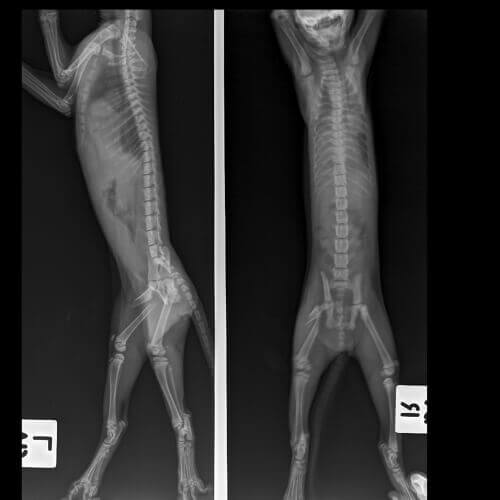

É necessário destacar a importância de obter o diagnóstico correto para que o gato não desenvolva distúrbios musculares ou nervosos permanentes. O seu veterinário fará um exame físico completo do seu gato para ajudar a determinar a localização exata do problema.

A idade do seu gato, o histórico de qualquer trauma, o início do problema (agudo ou crônico), a gravidade com que ele está mancando e se há várias patas envolvidas são indicadores da possível fonte do problema.

O diagnóstico para os gatos que estão mancando pode exigir exames especiais. Isso geralmente inclui um ou mais dos seguintes exames:

- Radiografias.